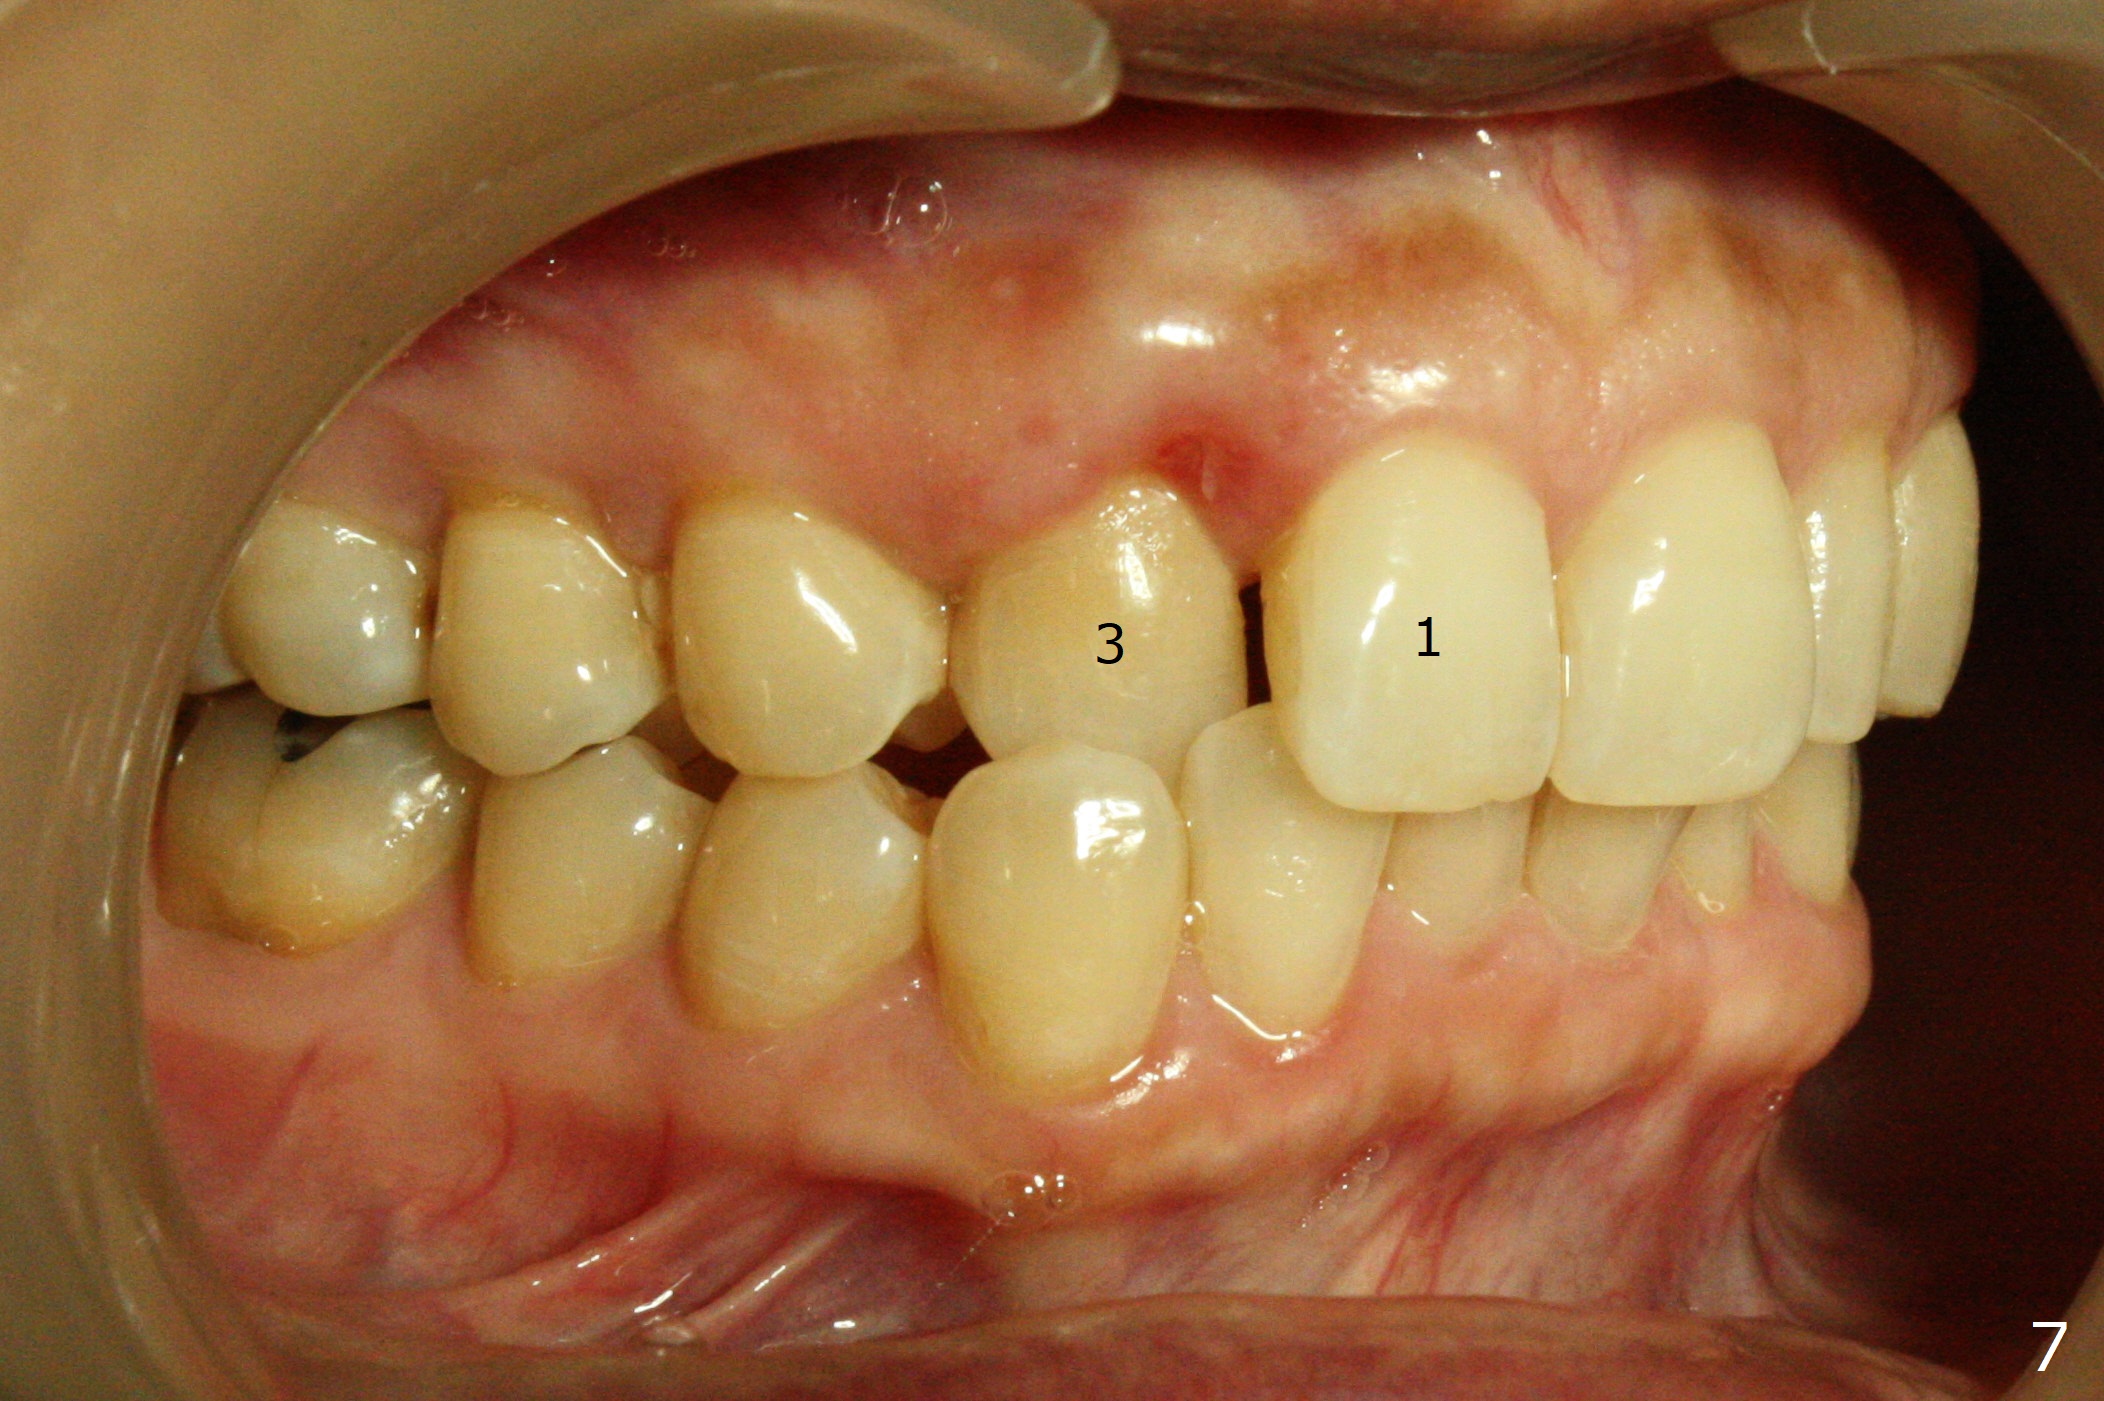

A 54-year-old woman (dento-phobic) will return for banding and bracketing 1.5 months post UR2 extraction with socket preser-vation. Lip strain is absent or minimal(Fig.1). The upper dental midline deviates to the right (Fig.2). Profile is within normal limit (Fig.3). UR3 is in cross bite (Fig.4). Cephalmetric X-ray apparently shows normal profile (Fig.5). Occlusion appears to be Class II in canine and molar (Fig.7,9, Class II Division II Malocclusion). The upper and lower dental midlines mismatch (Fig.8). UL2 is a peg lateral (Fig.10), while the lower anteriors are crowded (Fig.11). Arch wire sequence is conducted and let the timid patient decide whether the 2nd part of treatment should restore ideal occlusion with UR2 implant and UL2 veneer or simply close diastemata. Take PAs for the anteriors prior to banding to follow up root resorption during treatment.